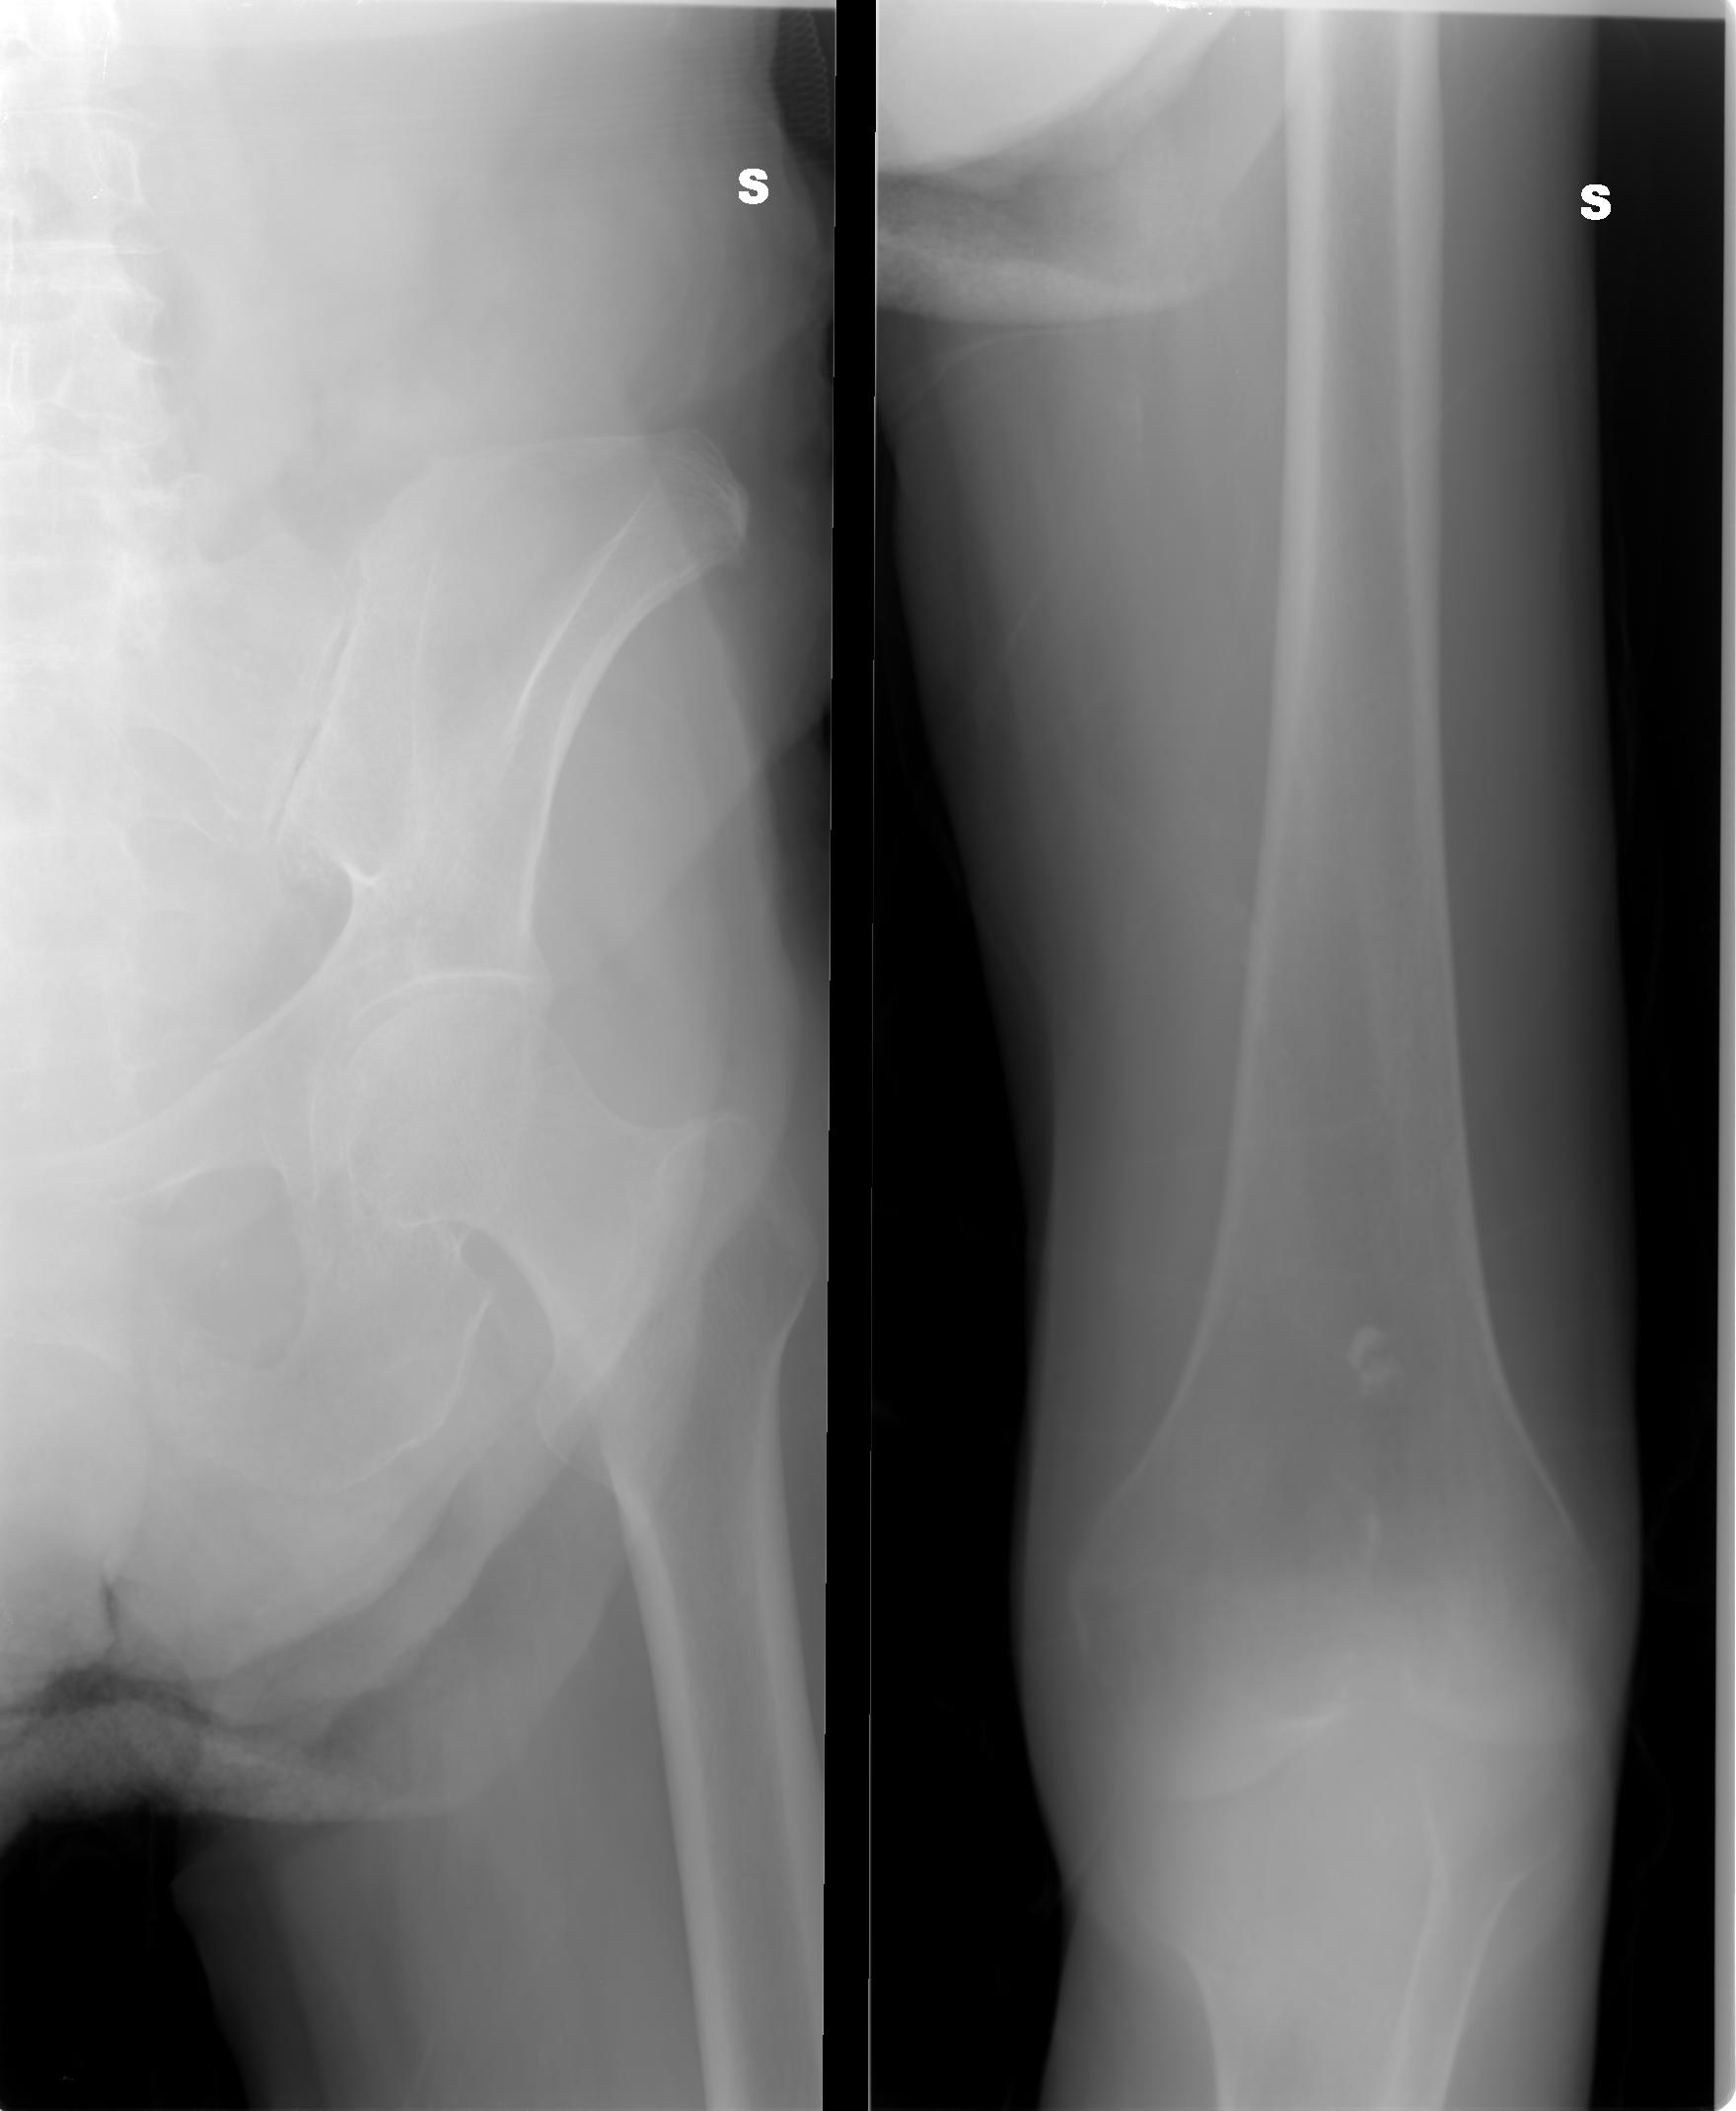

SALVE, ho ritirato un referto lastra per mia madre 80 anni e dice le seguenti parole: per quanto apprezzabile nel radiogramma a disposizione si osserva frattura composta della branca ile pubica sinistra .Sospetta frattura (o esiti fratturativi?) a carico dell branca ischio pubica omolaterale.

allego le lastre potete consigliarmi?

I00001.JPG

[ 123.31 KiB | Osservato 1195 volte ]